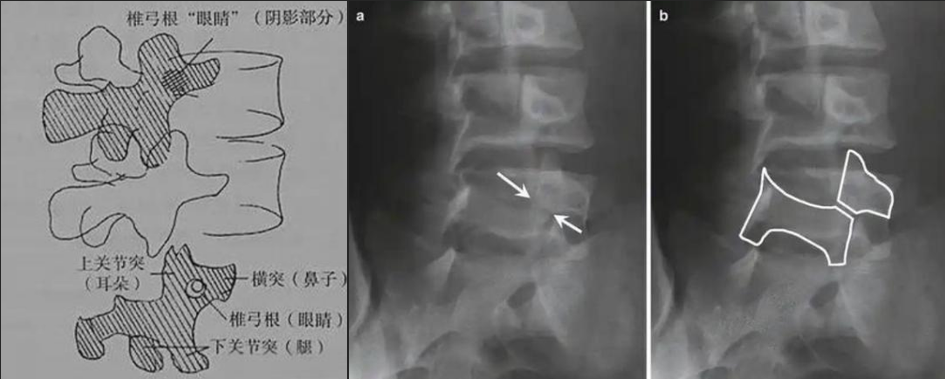

圖a和圖b 腰椎斜位:狗脖“戴項(xiàng)圈征”,診斷椎體椎弓峽部裂

椎弓根峽部是椎體后部椎弓上最狹窄、最薄弱、但應(yīng)力最集中的部位,在常規(guī)腰椎X線正側(cè)位上,因腰椎其他結(jié)構(gòu)的重疊顯示不清,但是在腰椎斜位上,能夠清楚完美地展現(xiàn)出來,若其在斜位片上表現(xiàn)為不連續(xù),則可診斷為椎弓根峽部裂,即腰椎的關(guān)鍵承重部分的骨質(zhì)斷裂,這是導(dǎo)致青少年和運(yùn)動(dòng)員腰痛的主要原因。

在腰椎斜位片上,腰椎的附件結(jié)構(gòu)形成了一個(gè)經(jīng)典的“斯科蒂狗”圖案,其中“狗脖子”處即代表椎弓根峽部,若“狗脖子”上出現(xiàn)了一條透亮清晰的線,就像給狗戴了一條“項(xiàng)鏈”,即“戴項(xiàng)圈征”,這是診斷椎弓峽部裂的直接證據(jù)。